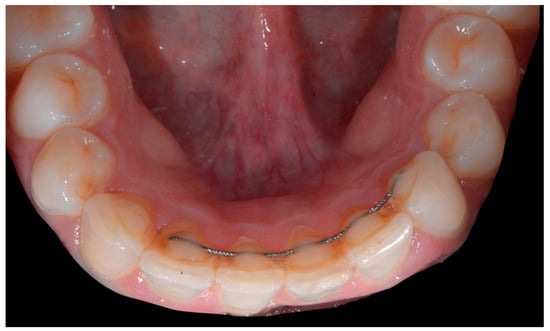

The occlusal views provide additional relevant information (Figure 9 and Figure 10). A maxillary retainer was present on 11 and 21 only and a difference in visibility of the vestibular surfaces (differential torque) on these same teeth was noted.

Figure 9.

Intermediate wire syndrome. Occlusal view.

Figure 10.

In the mandible, the retainer was broken distal to 42 and, despite being intact on 33, this tooth had increased visibility of its vestibular surface compared to its contralateral tooth (differential torque). Finally, teeth 31 and 41 also showed a difference in the visibility of their vestibular surfaces (differential torque). Ultimately, the patient was diagnosed with an X-effect wire syndrome on 21, an X-effect wire syndrome on 41, and a Twist-effect wire syndrome on 33.